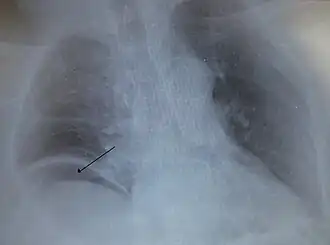

Причинами перфорации могут стать ножевое ранение, случайное употребление в пищу острого предмета, медицинская процедура, такая как колоноскопия, непроходимость кишечника, заворот кишечника, рак толстой кишки или дивертикулит, язва желудка, ишемия кишечника и ряд бактерий, включая Clostridioides difficile. При наличии данного образования кишечное содержимое проникает в брюшную полость. Проникновение бактерий приводит к состоянию, известному как перитонит, или к образованию абсцесса. Образование в желудке также может привести к химическому перитониту из-за проникновения желудочной кислоты. Компьютерная томография, как правило, является предпочтительным методом диагностики. Однако, свободный воздух из перфорации часто можно увидеть на обычном рентгеновском снимке.

На рентгеновских снимках в брюшной полости может быть виден газ. Он легко визуализируется на рентгеновском снимке, когда пациент находится в вертикальном положении. Перфорацию часто можно визуализировать с помощью компьютерной томографии. Лейкоциты часто повышены.